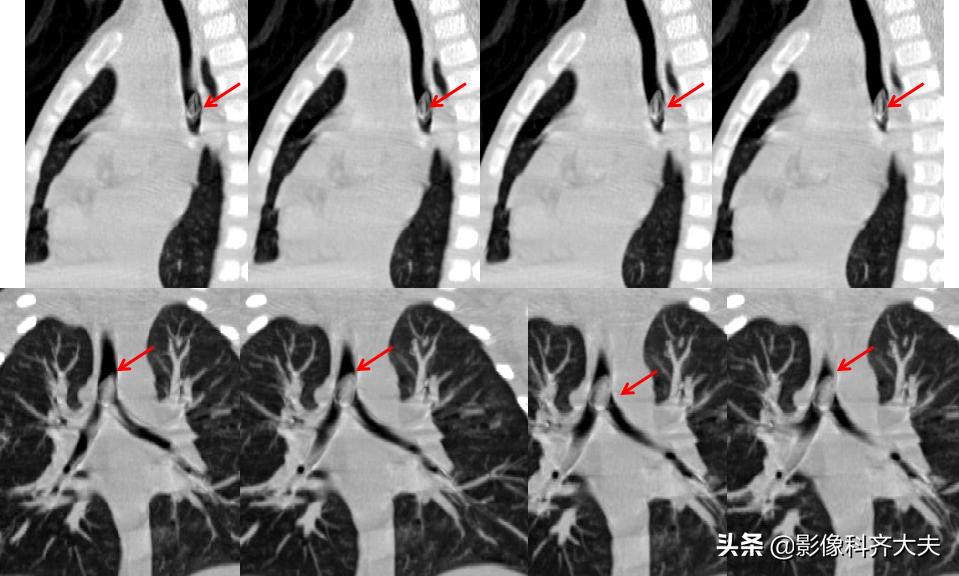

图为轴位及冠状位重建图显示异物:红色箭头为异物的位置,冠状位显示尤为清晰。

这是CPR(曲面重建),即单独对左侧支气管进行重建显影,清晰显示异物。

曲面重建后在进行最小密度投影重建,异物显示的更加清晰。